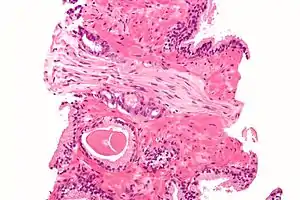

Cross-section of a nerve

Each nerve is covered on the outside by a dense sheath of connective tissue, the epineurium. Beneath this is a layer of fat cells, the perineurium, which forms a complete sleeve around a bundle of axons. Perineurial septae extend into the nerve and subdivide it into several bundles of fibres. Surrounding each such fibre is the endoneurium. This forms an unbroken tube from the surface of the spinal cord to the level where the axon synapses with its muscle fibres, or ends in sensory receptors. The endoneurium consists of an inner sleeve of material called the glycocalyx and an outer, delicate, meshwork of collagen fibres.[2] Nerves are bundled and often travel along with blood vessels, since the neurons of a nerve have fairly high energy requirements.

Within a nerve, each axon is surrounded by a layer of connective tissue called the endoneurium. The axons are bundled together into groups called fascicles, and each fascicle is wrapped in a layer of connective tissue called the perineurium. Finally, the entire nerve is wrapped in a layer of connective tissue called the epineurium. Nerve cells (often called neurons) are further classified as sensory, motor, or mixed nerves.